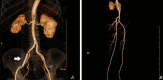

Figure 6. Post-procedure reconstructed CT angiogram of the lower limbs

(A) Good stent position (white arrow) and no residual leak. (B) Good distal perfusion and patent stent.